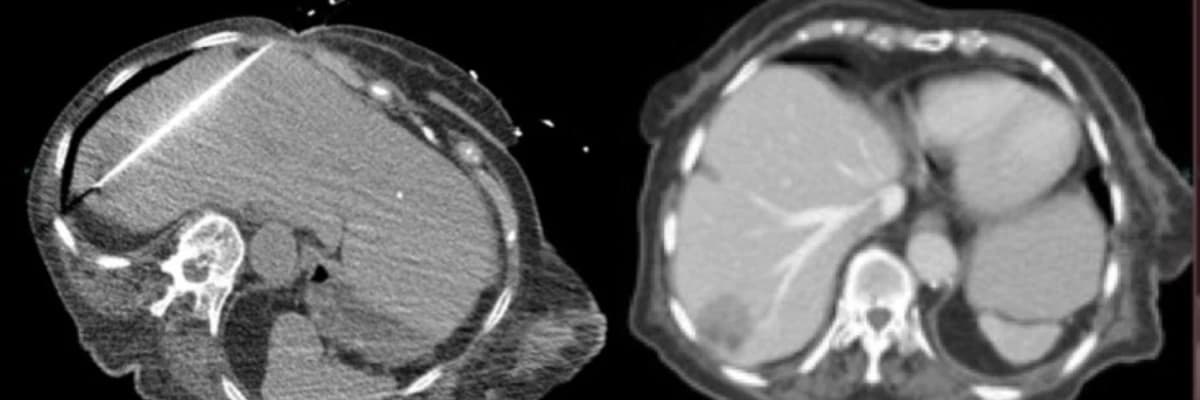

KARACİĞER KANSERLERİNDE ABLASYON

Cerrahi Yapılamayan Kolorektal Karaciğer Metastazlarında Lokal Tedavi Yaklaşımları

Cerrahi uygulanamayan kalın bağırsak karaciğer metastazlarında tümör ablasyonu sıklıkla tercih edilen bir yöntemdir. Ancak, bu yöntemin toplam yaşam süresine sağladığı katkı daha önceki randomize çalışmalarda net bir şekilde ortaya konulmamıştı. Yeni paylaşılan Randomize Faz II çalışma sonuçları, bu alandaki tedavi protokolleri için kritik veriler sunmaktadır.